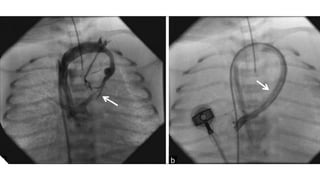

CARDIAC CATHERISATION

• Always Diagnostic

• Indication

✦ Measure PVRI / Reversibility in older children

✦ Diagnosis not clear on Echocardiography

✦ Intervention - BAS, PV dilatation, Vertical Vein Dilatation

• PA/PV Angiogram

✦ PA injection with venous follow through preferred over direct PV injection

✦ Anatomy of TAPVC

✦ Type

✦ Drainage

✦ Site of Obstruction

IC-TAPVC CATHTER ANGIO